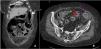

Quince meses después, la paciente experimentó una perforación ileal terminal espontánea, diagnosticada mediante TC (fig. 1), complicada con peritonitis fecaloidea y bacteriemia (Bacteroides fragilis). La presentación clínica incluyó vómitos y dolor abdominal agudo, con elevación de PCR, realizándose resección ileal con anastomosis laterolateral, con conversión posterior a ileostomía terminal por dehiscencia anastomótica y recuperación postoperatoria favorable. El análisis histopatológico reveló inflamación, congestión vascular y fibrosis en pared ileal, sin signos de malignidad. Sarilumab fue suspendido antes de la cirugía, reintroduciéndose colchicina, sin ulteriores brotes durante 18 meses. Sin embargo, posteriormente la paciente progresó a artritis reumatoide (AR), iniciándose tratamiento con MTX y dosis bajas de glucocorticoides (GC). Desde la intervención hasta el momento actual y durante un período de seguimiento de 2 años, la paciente se ha mantenido clínicamente asintomática, sin nuevos episodios de dolor abdominal.

Extenso neumoperitoneo difuso asociado a importante cantidad de líquido libre de predominio en espacios parietocólicos de predominio izquierdo (flecha blanca). En el íleon-distal (a aproximadamente 10-15cm de la válvula ileocecal) se aprecia una solución de continuidad parietal de 5mm, sugestiva de perforación (flecha roja).